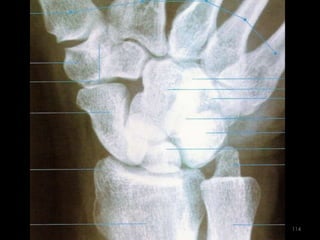

Incidência AP e PA do Punho88

89

90

Incidência lateral (perfil) do punho (látero-medial)91

92

93